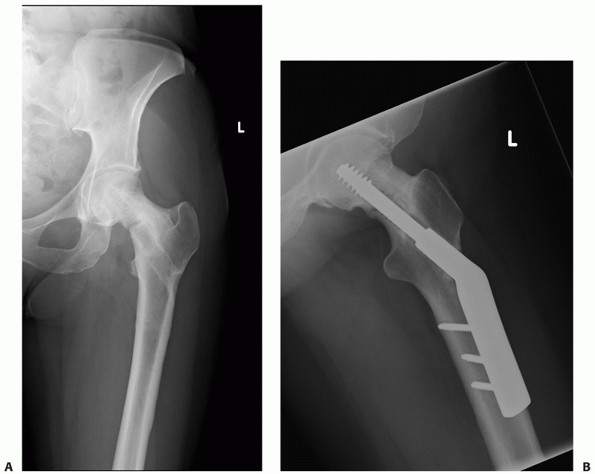

![]() |

|

FIGURE 47-9 A. AP and (B) lateral radiographs of a displaced intracapsular hip fracture well-healed 9 months after fixation with three cannulated screws.

treatment of choice for the undisplaced intracapsular hip fracture.

There are a large number of implants available from which to choose. In

modern orthopaedic practice the usual choice is either a cannulated

screw system (Fig. 47-9) or a sliding hip screw device with a short plate. These have superseded older devices such as hook pins,241 Knowles pins,238 and the Watson-Jones nail,195 even though these implants were documented as having results comparable with more modern implants.